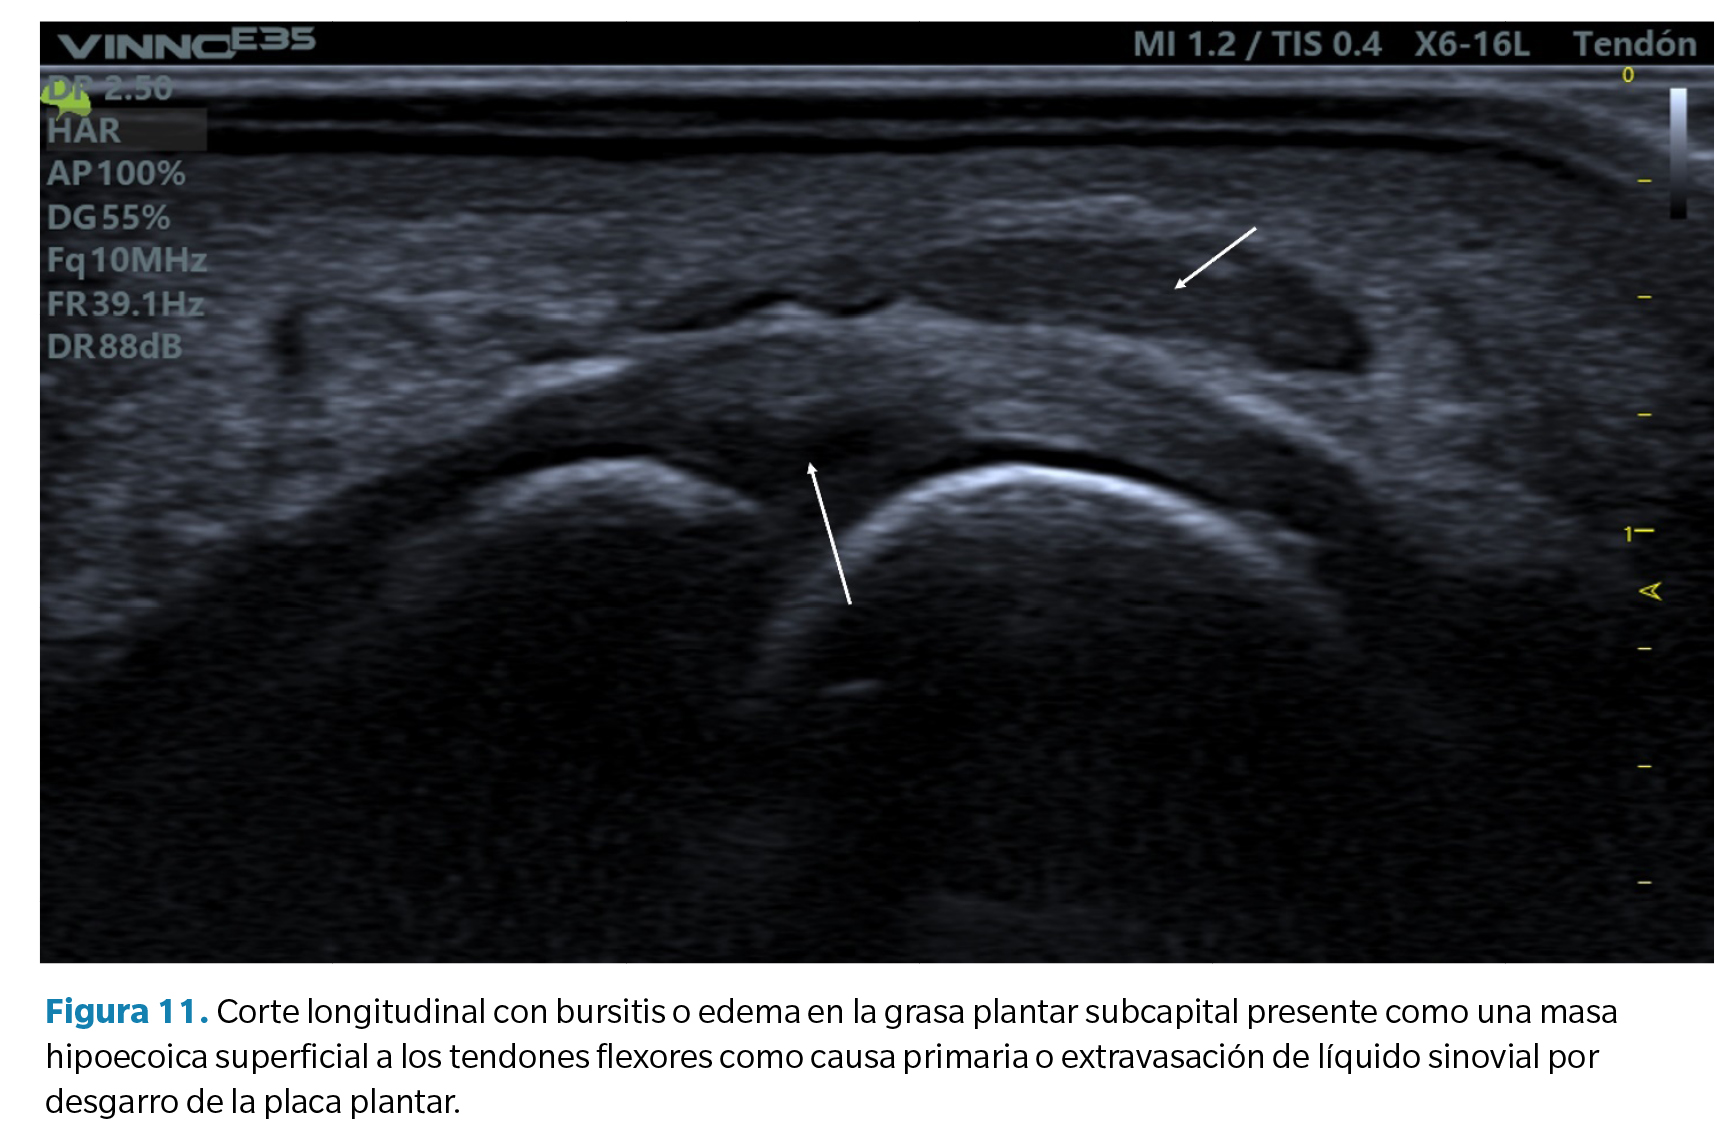

2. Bursitis de la grasa plantar. En relación con el hallazgo anterior, algunos casos de desgarros de la placa plantar pueden acompañarse también de un infiltrado hipoecoico en la grasa plantar adyacente. Esto puede ser un defecto primario del exceso de compresión sobre dicha grasa (compresión que también forma parte de la etiología de lesión compresiva de la placa) o bien el resultado de un infiltrado de líquido sinovial por extravasación de la rotura capsular como se ha comentado anteriormente. Es frecuente en estos casos advertir la presencia de un doppler positivo (Figura 11).